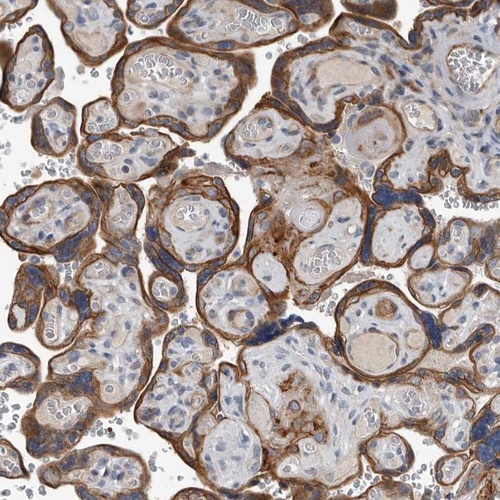

Immunohistochemical staining of human placenta shows distinct cytoplasmic and membranous positivity in trophoblasts.